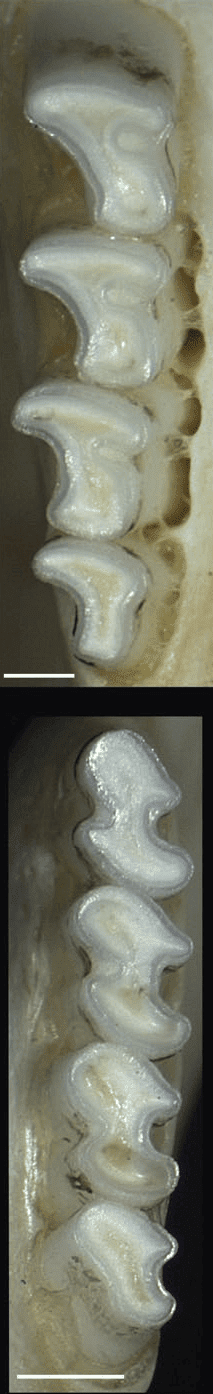

Troubles des prémolaires et molaires chez les degus.

(A) Allongement coronal avec formation d’éperons de la première dent de la joue mandibulaire droite.

(B) Allongement coronal bilatéral de la première dent prémolaire mandibulaire, avec formation typique d’un éperon mandibulaire, d’un « pont » et piégeage ultérieur de la langue. (Vladimir Jek)